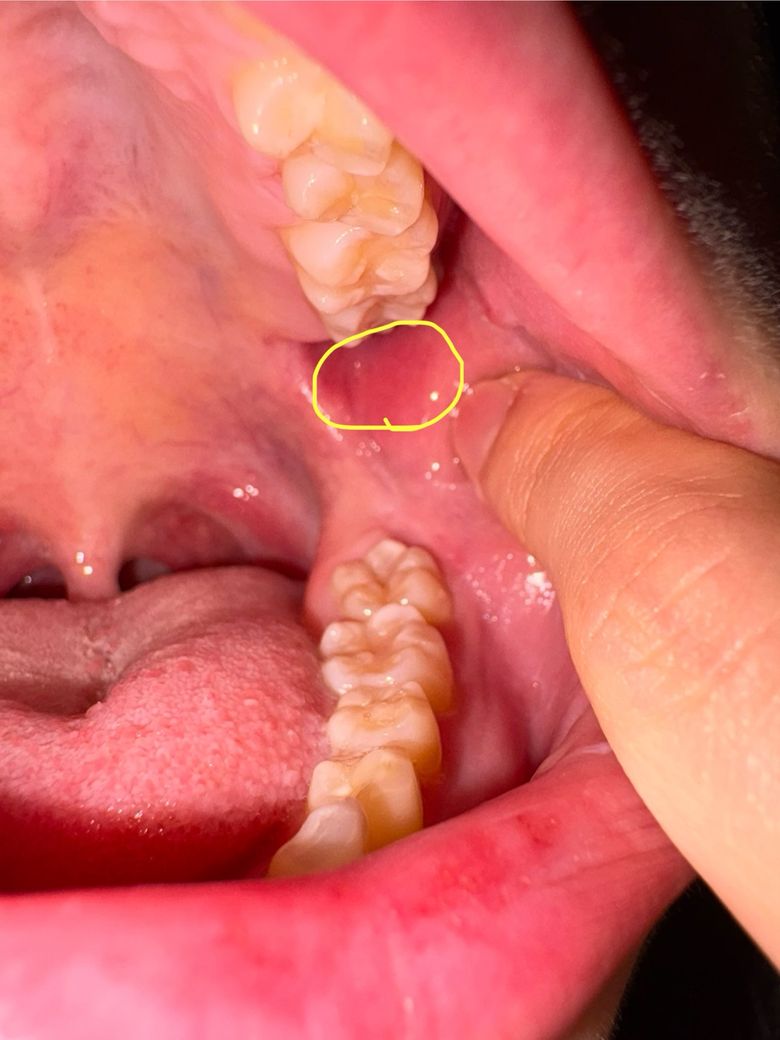

정확히 저 노랑색으로 동그라미 친 부분이 아픈데

이빨이 나는 자리도 아니고 어금니 뒤쪽 볼 안 쪽?

부분이 너무 아픈데 왜일까요ㅜㅜ

구내염처럼 보이는건 없는것 같은데 뭘까요..

• 1번 째 사진

사진에 보이는건 볼살이 치아에 씹혀서 상처가 생긴거 같습니다. 계속 불편하시면 사랑니 떄문에 그럴수 있으니 사랑니 검진을 먼저 받아보세요.

현재로서는 구내염일 수도 있으나 해당 부분에 치아로 인하여 나타나는 상처일 수 있습니다. 현재 사진에서는 보이지 않지만 위쪽 어금니 뒤쪽에 사랑니가 있다면 해당 사랑니로 인하여 아랫부분에 지속적으로 상처가 생겨서 나타나는 상황일 수 있습니다. 지속적인 불편감이 있다면 가까운 치과 방문 후 상담을 권해드립니다.

1. 사진상 약하게 발적이 보이네요